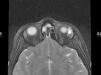

El linfangioma es una malformación linfática cuyo tratamiento habitual ha sido la cirugía. Se aporta un caso de linfagioma orbitario en una niña a la que se trató con OK-432 intralesional para evitar la cirugía y sus complicaciones.

Lymphangioma is a malformation of the lymphatic system. The classic approach is surgery. We report a case of orbital lymphangioma in a girl who was given OK-432 to avoid surgery and its complications.